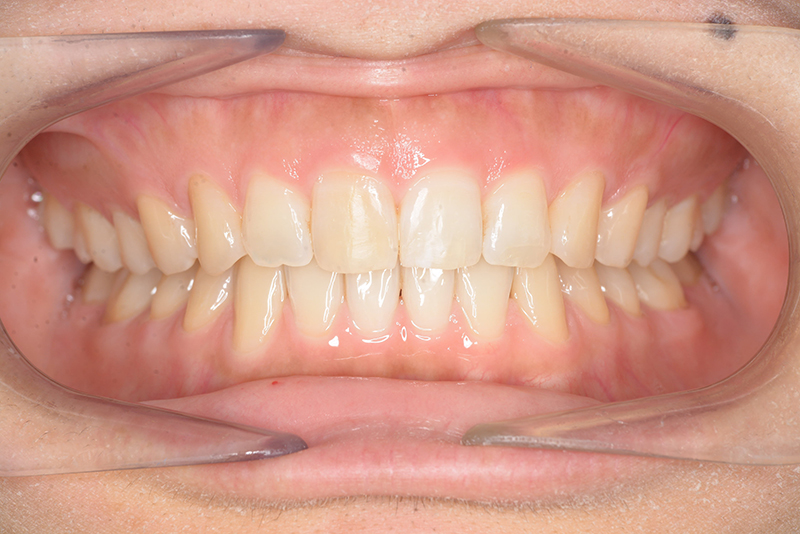

動的治療終了時

FP・IOP

批評・予后 上顎臼歯は軽度に近心傾斜しつつ、歯列遠心部には奥行きがあり、下顎歯列には叢生は認められず、スピー湾曲も軽度であること。また軟組織上の問題もないため、上顎歯列の遠心移動による治療が妥当だと判断した。治療後において上顎歯列の遠心傾斜と共に下顎はカウンタークロックワイズローテーションをしながら咬合の緊密化が得られた。